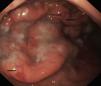

La endoscopia mostró en todos engrosamiento de pliegues gástricos, sobre todo de fundus y cuerpo (fig. 1), asociado en los pacientes 3 y 4 a erosiones más o menos extensas (fig. 2). El estudio histológico demostró infiltrado inflamatorio agudo y edema con hiperplasia del epitelio gástrico y dilatación glandular. El estudio inmunohistoquímico fue positivo en 2 pacientes.

Endoscópicamente, se aprecia engrosamiento de los pliegues gástricos, con diferentes grados de inflamación mucosa, pudiéndose llegar a producir ulceraciones gástricas severas10,19, como las observadas en los pacientes 2 y 3 de nuestra serie. Histológicamente, los hallazgos son similares a la EM del adulto, caracterizándose por hipertrofia e hiperplasia del epitelio gástrico, con engrosamiento de la mucosa por proliferación, elongación y dilatación quística de glándulas gástricas, con hipersecreción, edema e infiltrado inflamatorio4.